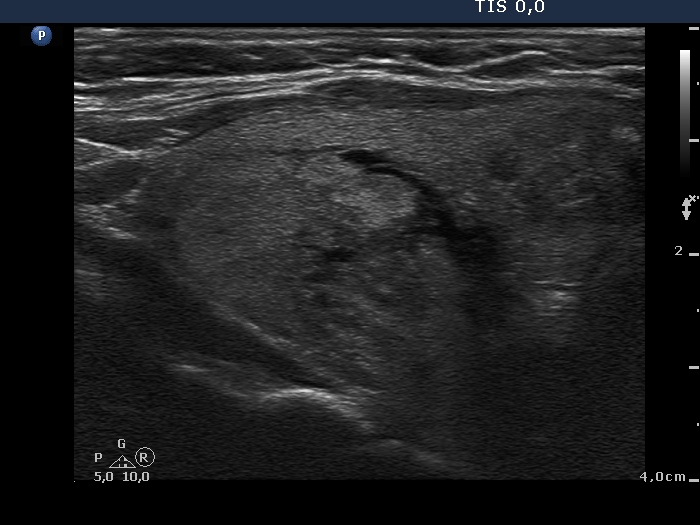

Ultrasonography. There were two nodules in the left lobe. The upper one was echonormal while the lower hypoechogenic one contained microcalcification and a cotton-like larger hyperechogenic patch and presented an irregular shape and an intranodular vascularity.